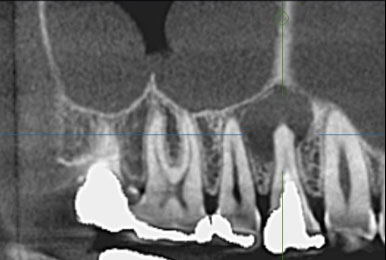

主訴: 噛むと痛い、左で食べれない。他の病院で神経が見つからない。根の先に病気がある。

通常だと手立てがなく、抜歯しかない歯も外科(根尖切除術)で治すことができます。

歯茎が腫れ、CT上では骨が大きくないことがわかります